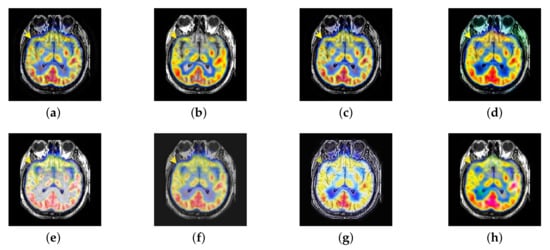

In this section, there are four multi-modal image sets and each set is consist of MRI image and SPECT image that are corresponding to the sanme location slice of the brain as shown in Figure 7. Among them, Figure 7e,f are captured from patients who have suffered a subacute stroke. Figure 7a–d,g,h are captured from patients who have brain tumor. The fused images with different fusion methods based on DTCWT, NSCT, GFF, LPSR, IGM, DDcGAN, FusionCNN, and the proposed methods are shown in Figure 8, Figure 9, Figure 10 and Figure 11. It can be seen that the fused images obtained by LPSR and FusionCNN algorithm have serious color distortion. Based on DTCWT and NSCT algorithm, the fusion image structure information is not obvious. The fused images obtained by GFF and IGM algorithm contain almost no color information, which is not conducive for doctors to make correct diagnosis. The image obtained by the DDcGAN algorithm saves the color information in the SPECT to a great extent; however, the brightness of the fused image is too large, which causes the image to have no sense of hierarchy and the contrast to decrease. By comparing with other algorithms, we find that our algorithm has good color retention effect, clear structure information, moderate brightness, and no artifacts.

Figure 8.

Fused medical images obtained by different algorithms (Figure 7a,b): (a) dual tree complex wavelet transform (DTCWT), (b) guided filtering fusion (GFF), (c) non-subsampled contourlet transform (NSCT), (d) Laplacian pyramid sparse representation (LPSR), (e) internal generative mechanism (IGM), (f) Fusion convolutional neural network based (FusionCNN), (g) dual-discriminator conditional generative adversarial network based (DDcGAN), and (h) FusionNet.

Figure 9.

Fused medical images obtained by different algorithms (Figure 7c,d): (a) DTCWT, (b) GFF, (c) NSCT, (d) LPSR, (e) IGM, (f) FusionCNN, (g) DDcGAN, and (h) FusionNet.

Figure 10.

Fused medical images obtained by different algorithms (Figure 7e,f): (a) DTCWT, (b) GFF, (c) NSCT, (d) LPSR, (e) IGM, (f) FusionCNN, (g) DDcGAN, and (h) FusionNet.

Figure 11.

Fused medical images obtained by different algorithms (Figure 7g,h): (a) DTCWT, (b) GFF, (c) NSCT, (d) LPSR, (e) IGM, (f) FusionCNN, (g) DDcGAN, and (h) FusionNet.